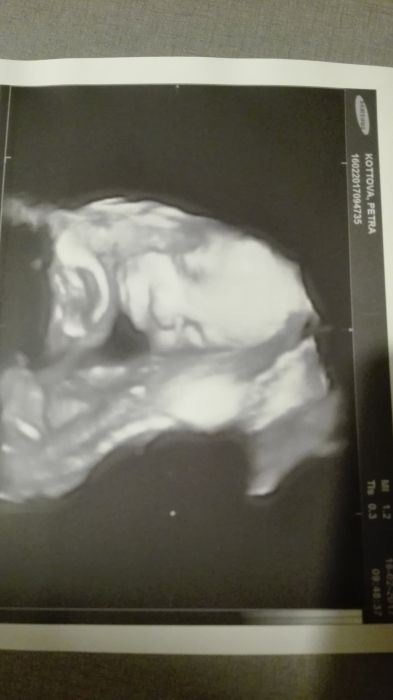

Ahoj holky, včerejší kontrola a ultrazvuk dopadl dobře. Malé mělo pěkně kulaťoučké bříško a špulilo na mne rtíčky. Krásný pohled :) Mimčo se uvelebilo dnem pánevním, ale stále věřím, že se ještě otočí do správné polohy (jak jsem tu už psala o moji mamči a bráchovi, tak to dno pánevní máme asi v genech :D), místa tam má ještě dost a podle toho,jak tam řádí, to nebude problém ;)

Ahoj, jen rychle na skok zprávy o nas. Dnes UTZ, 31+3, 1800g, hlavička dole, super zprávy :-) Gratuluji vašim k super zprávám :-) Váhu vám ani nebudu psát, mám nahore málo, ale váha miminka mě uklidnila, nevím z čeho roste, ale roste :-) Pokojíček budeme mít koncem března, nakonec komplet od truhlaru, uz jsou postele, chybí skrin a vylepit tapety. Papíry všechny vyřízené a za 14 dni monitory, to uz chci mít vše nachystané ten měsíc před, ať je klid, pro jistotu. Mějte se fajn!